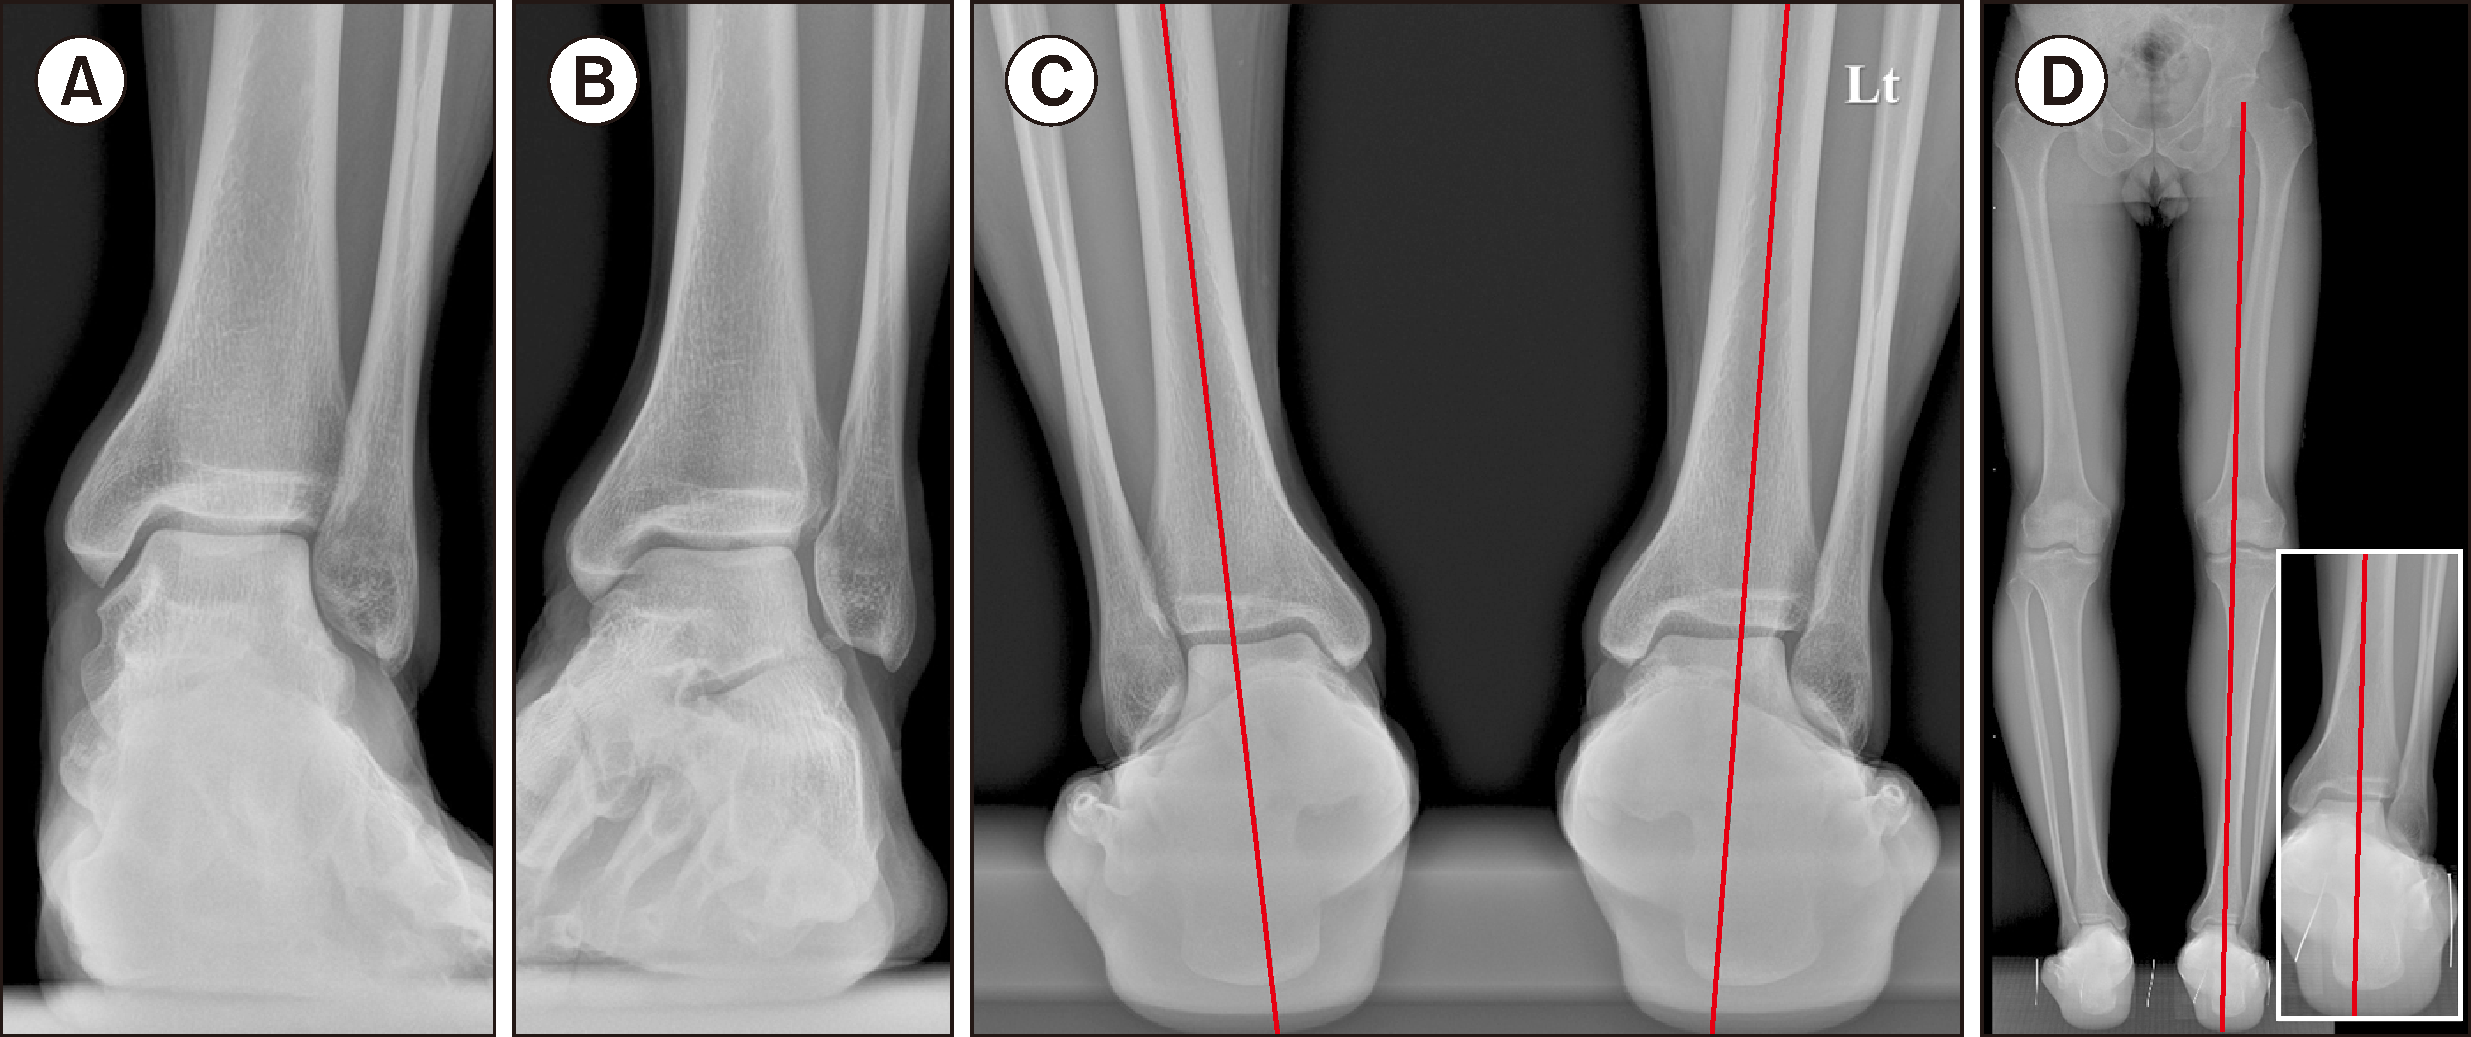

Figure 1

Radiographic findings of the ankle and hindfoot alignment. On weight-bearing anteroposterior radiograph of the ankle (A), a valgus tilt of the talus at 3.9° was shown and the mortise view (B) suggested the existence of os subfibulare and widening of the syndesmosis. Hindfoot alignment view (C) present a valgus deviation of the hindfoot with more pronounced valgus tilt of the talus compared to the anteroposterior radiograph. Likewise, hip-to-calcaneus radiograph (D) also demonstrated a slight valgus deviation of the hindfoot relative to the overall axis of the lower limb.

통증의 양상을 보다 정확히 확인하기 위하여 시행한 문진상, 좌측 발목 내측 및 외측 모두에 뻐근한 통증이 존재하였으며, 외측이 내측보다 조금 더 심한 양상이었다. 발목 외측의 통증은 내원 1년 전 처음 접질린 당시부터 현재까지 강도의 변화는 있었지만 꾸준히 존재해왔다고 하며, 발목 내측의 통증은 내원 4개월 전 계단에서 크게 접질린 이후부터 새롭게 발생하였다고 설명하였다. 신체 진찰상 전신 관절의 유연성7)은 확인되지 않았으며, 발목 부위의 압통은 외과의 전거비인대 부착 부위 및 원위 경골의 전하경비인대 부착부위에서 가장 심하였고, 발목 내과 첨부에서도 압통을 호소하였다. 체중부하 족관절 전후면 방사선 사진상 3.9°의 외반거골 경사가 확인되었으며(Fig. 1A), 격자면 사진상 비골하 부골 및 원위경비인대 결합 부위의 이개(diastasis)가 의심되었다(Fig. 1B). 후족부 정렬상에서 족관절 전후면 사진에 비하여 외반거골 경사가 더욱 두드러지게 확인되었으며, 후족부 역시 외반위로 정렬되어 있었다(Fig. 1C). 하지 전체의 축을 확인하기 위해 시행한 hip-to-calcaneus 사진상에서도 하지 전체의 축에 비하여 후족부가 약간 외반위로 위치하고 있음을 관찰할 수 있었다(Fig. 1D).